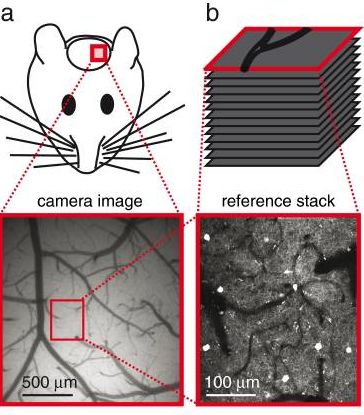

下图为ImageJ官网示例Stack图片t1-head.tiff,2维图像(XY视图)窗口如左侧窗口(256 x256),当前Slice为129张图片的第58张。t1-head.tiff图片属性如右图所示:

图片属性可通过Image -> Properties得到: